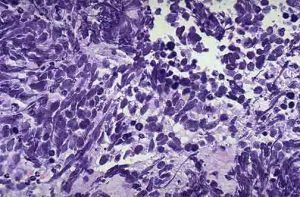

燕麥細胞癌隸屬於小細胞肺癌的亞型分支,而小細胞肺癌是肺癌的兩大部分之一,平均每五名肺癌患者就有一名是小細胞肺癌(SCLC)。值得注意的是,燕麥細胞癌在電鏡下胞質內可見神經內分泌顆粒,神經分泌顆粒見於全部5例燕麥細胞癌亞型,在中間細胞型癌亞型6/8例陽性,因此燕麥細胞癌也屬肺神經內分泌癌。